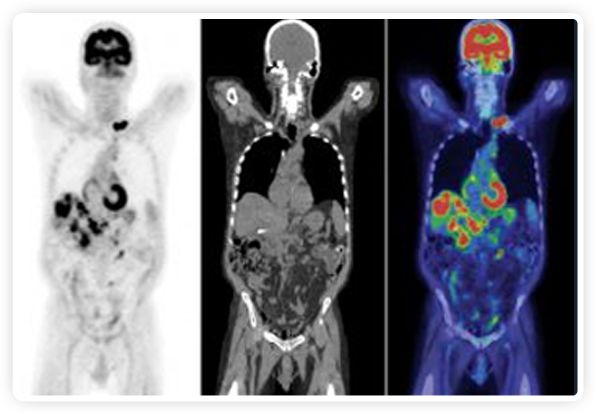

PET+放療共同治療

RefleXion將PET成像與立體定向放射治療相結(jié)合。在注射示蹤劑后,RefleXion的技術(shù)基于示蹤劑信號實(shí)時(shí)地在一個(gè)或多個(gè)目標(biāo)上引導(dǎo)治療性X射線。使用這種專有方法,RefleXion的平臺有可能比現(xiàn)有系統(tǒng)向癌癥病變提供更高劑量的輻射,并改善周圍健康組織的保護(hù)。

有這么大的潛力,為什么以前沒有做過?一個(gè)原因是使用傳統(tǒng)PET技術(shù)生成高質(zhì)量圖像需要的時(shí)間較長,這使得它不適合實(shí)現(xiàn)實(shí)時(shí)器官運(yùn)動(dòng)追蹤。

為了避免PET長圖像采集時(shí)間,RefleXion開發(fā)了一項(xiàng)專利技術(shù)使用重合的PET光子對來指導(dǎo)放射治療束,因?yàn)閷?shí)時(shí)檢測發(fā)射的光子,為生物指導(dǎo)提供了一種時(shí)間有效的方法。